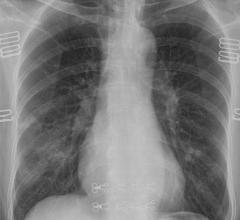

This page contains medical information for clinicians on the 2019 Novel Coronavirus (COVID-19, also called 2019-nCoV and now clinically SARS‐CoV‐2). This section includes articles on medical imaging of the virus for radiologists, new technologies being deployed to fight the virus and clinical information from various sources. Here are direct links for medical professionals to COVID-19 resources from the U.S. Food and Drug Administration (FDA), Centers for Disease Control (CDC) and the World Health Organization (WHO). Daily world-wide statistics on the coronavirus outbreak are available from the WHO Situations Reports. Centers for Medicare and Medicaid Services (CMS) frequently asked questions and answers (FAQs) for healthcare providers regarding Medicare payment for laboratory tests and other services related to the COVID-19

July 10, 2020 — An open-access American Journal of Roentgenology (AJR) article investigating the differences in computed ...